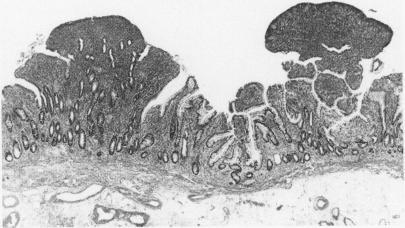

Ileostomy polyps are uncommon and poorly described. The aim of this study was to undertake a retrospective clinicopathological review of ileostomy polyps. Seven patients with 60 polyps arising on ileostomies performed for ulcerative colitis were studied. The histopathological evaluation of archival ileostomy biopsy specimens, polypectomy or excision specimens, and clinical review of patient records was undertaken. Fifty of 60 polyps were inflammatory cap polyps and six further polyps were composed of granulation tissue only. They occurred anywhere on the stoma at any time after ileostomy construction and were strongly associated with overt stomal prolapse. Four neoplastic polyps were identified in two patients 27-36 years after ileostomy construction; all occurred at the mucocutaneous junction. One patient presented with a 2 cm polypoid invasive adenocarcinoma while in the second a 1.7 cm polypoid mucinous adenocarcinoma and a 0.7 cm ileal tubular adenoma with high grade dysplasia occurred at the site of excision of a cap polyp showing focal low grade adenomatous dysplasia six years previously. Neoplastic and non-neoplastic polyps could not be differentiated clinically. It was found that most ileostomy polyps are inflammatory cap polyps associated with stomal prolapse. Less common are polypoid adenomas or adenocarcinomas arising at the mucocutaneous anastomosis > 20 years after ileostomy construction. To prevent ileostomy carcinoma it is recommended that a biopsy of all polyps at the mucocutaneous anastomosis and of any non-prolapse associated polyps elsewhere on the stoma occurring > 15 years after ileostomy construction is done.

回肠造口息肉并不常见,且相关描述较少。本研究的目的是对回肠造口息肉进行回顾性临床病理分析。我们研究了7例因溃疡性结肠炎行回肠造口术且出现60个息肉的患者。对存档的回肠造口活检标本、息肉切除术或切除标本进行了组织病理学评估,并对患者记录进行了临床回顾。60个息肉中有50个为炎性帽状息肉,另外6个息肉仅由肉芽组织构成。它们在回肠造口术后的任何时间出现在造口的任何部位,且与明显的造口脱垂密切相关。在回肠造口术后27 - 36年,在2例患者中发现了4个肿瘤性息肉;所有息肉均发生在黏膜皮肤交界处。1例患者出现了一个2 cm的息肉样浸润性腺癌,而在另1例患者中,在6年前切除的一个显示局灶性低级别腺瘤样发育异常的帽状息肉部位,出现了一个1.7 cm的息肉样黏液腺癌和一个0.7 cm的伴有高级别发育异常的回肠管状腺瘤。肿瘤性息肉和非肿瘤性息肉在临床上无法区分。研究发现,大多数回肠造口息肉是与造口脱垂相关的炎性帽状息肉。较少见的是在回肠造口术后20多年在黏膜皮肤吻合处出现的息肉样腺瘤或腺癌。为预防回肠造口癌,建议对回肠造口术后15年以上在黏膜皮肤吻合处的所有息肉以及造口其他部位任何与脱垂无关的息肉进行活检。